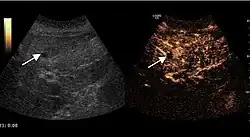

The ultrasound appearance is a well defined lesion, with very thin, almost unapparent walls, without circulatory signal at Doppler or CEUS investigation. The content is transonic suggesting fluid composition. The presence of membranes, abundant sediment or cysts inside is suggestive for parasitic, hydatid nature. Posterior from the lesion the acoustic enhancement phenomenon is seen, which strengthens the suspicion of fluid mass. They typically displace normal liver vessels but no vascular or biliary invasion occurs.

Hydatid liver cyst. Diagnostic criteria are the presence of membranes and sediment inside.